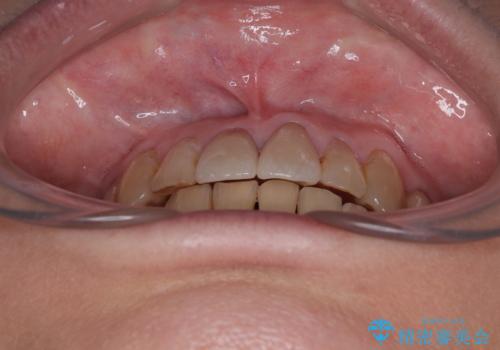

歯肉移植などによる前歯部の歯肉ライン改善を提案しましたが、口を開けたときにほとんど見えないので気にならないとのことで、特に処置を行うことなく補綴治療を行いました。